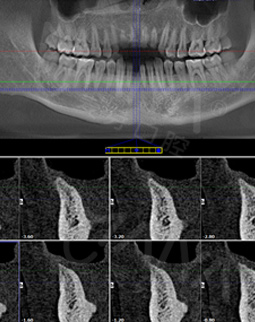

经过数字化的拍片检查后发现,我的牙周情况还是蛮不错的,可以用MAC数字化精确种植牙实现8分钟种稳一颗牙,而且工作人员说我可以作为直播案例主角分享自己的故事,感到非常荣幸。

在种牙之前,这里的硕博专家给我讲解了种植牙的相关知识,而且通过数字化的设备模拟出种牙的全过程,打消了我的种种疑虑。专家说,随着数字化在口腔领域的应有,种牙已经不像之前那样等待时间长、创口大、步骤多,而是实现即种即用,并且利用数字化导航设备种牙更精确,不用仅仅依靠医生经验去进行种牙,手术前一周我已经做了取模,今天准备种牙!